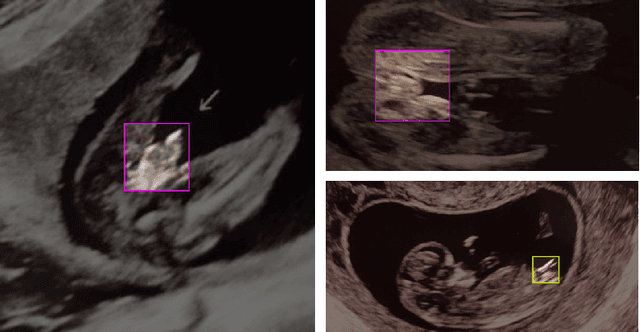

Abstract:Ultrasound (US) imaging is highly effective with regards to both cost and versatility in real-time diagnosis; however, determination of fetal gender by US scan in the early stages of pregnancy is also a cause of sex-selective abortion. This work proposes a deep learning object detection approach to accurately mask fetal gender in US images in order to increase the accessibility of the technology. We demonstrate how the YOLOv5L architecture exhibits superior performance relative to other object detection models on this task. Our model achieves 45.8% AP[0.5:0.95], 92% F1-score and 0.006 False Positive Per Image rate on our test set. Furthermore, we introduce a bounding box delay rule based on frame-to-frame structural similarity to reduce the false negative rate by 85%, further improving masking reliability.